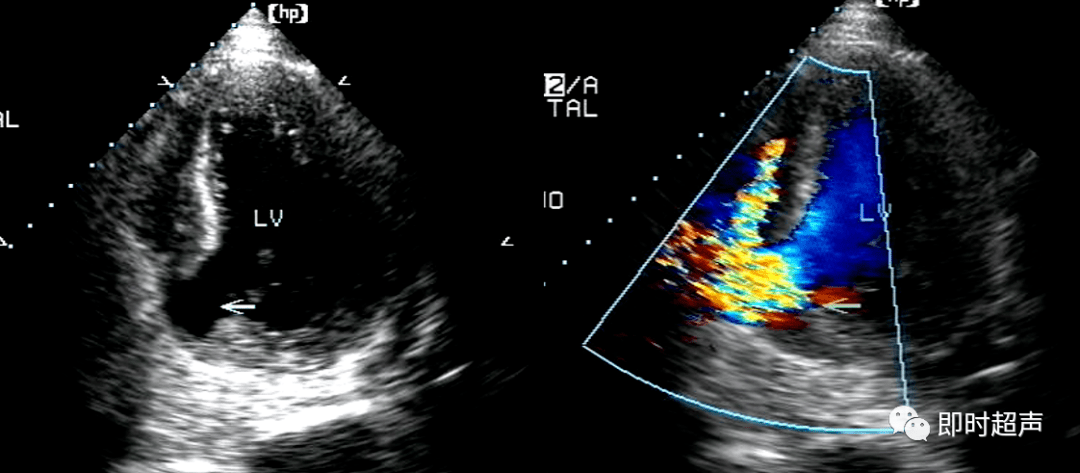

心肌梗死常见并发症超声诊断_二尖瓣_心动图_运动